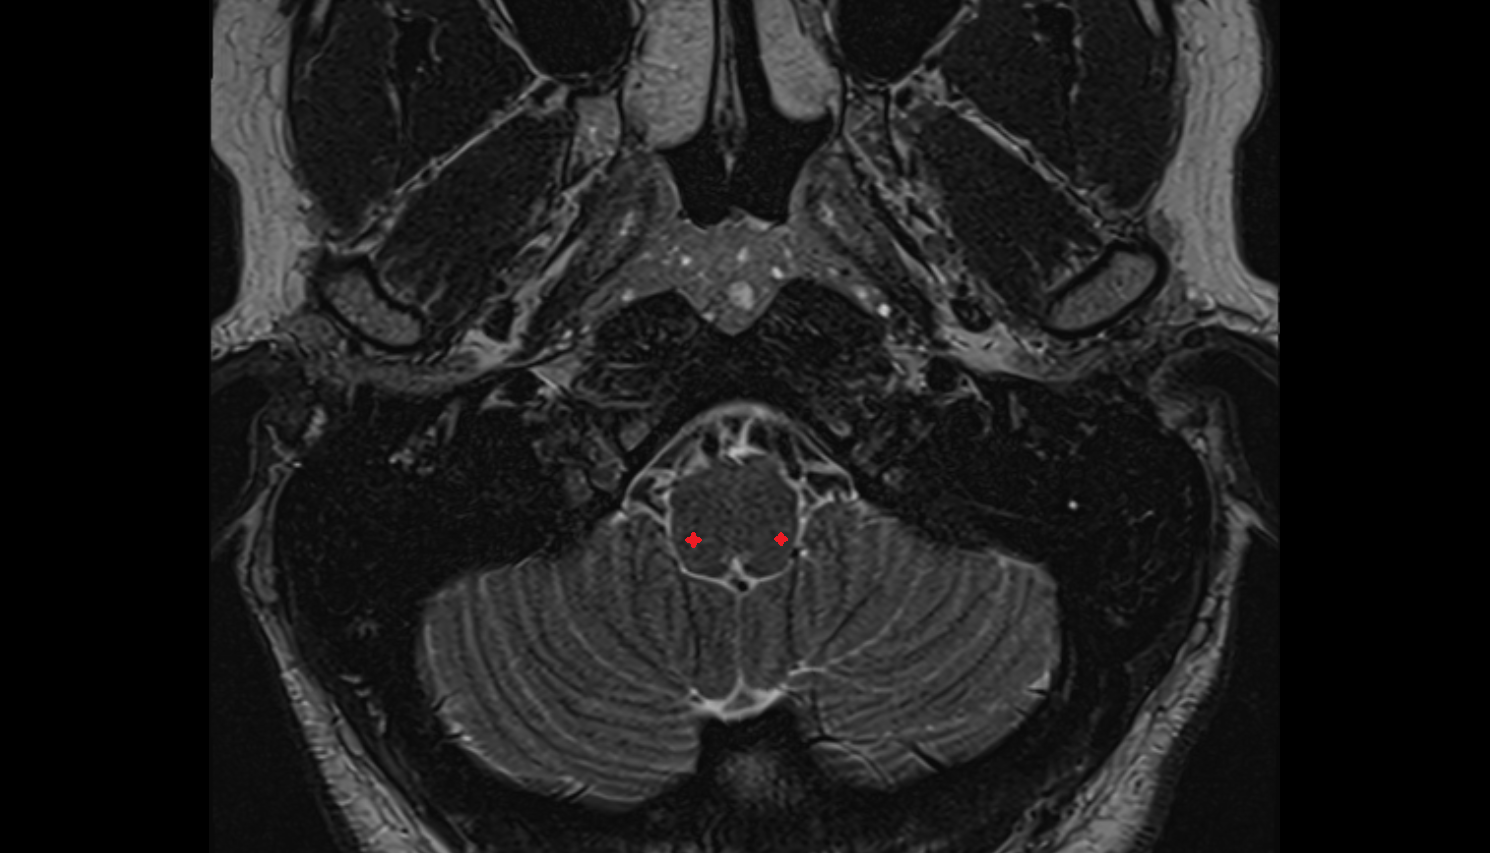

- Cerebellum

- Dentate nucleus

- Flocculus

- Crus I of ansiform lobule of cerebellum

- Crus II of ansiform lobule of cerebellum

- Paramedian lobule (HVII) of cerebellum

- Simple lobule (HVI) of cerebellum

- Anterior quadrangular lobule (HV) of cerebellum

- Anterior quadrangular lobule (HlV) of cerebellum

- Biventral lobule (HVIII) of cerebellum

- White matter of cerebellum (Arbor vitae)

- Cerebellar tonsil (H IX)